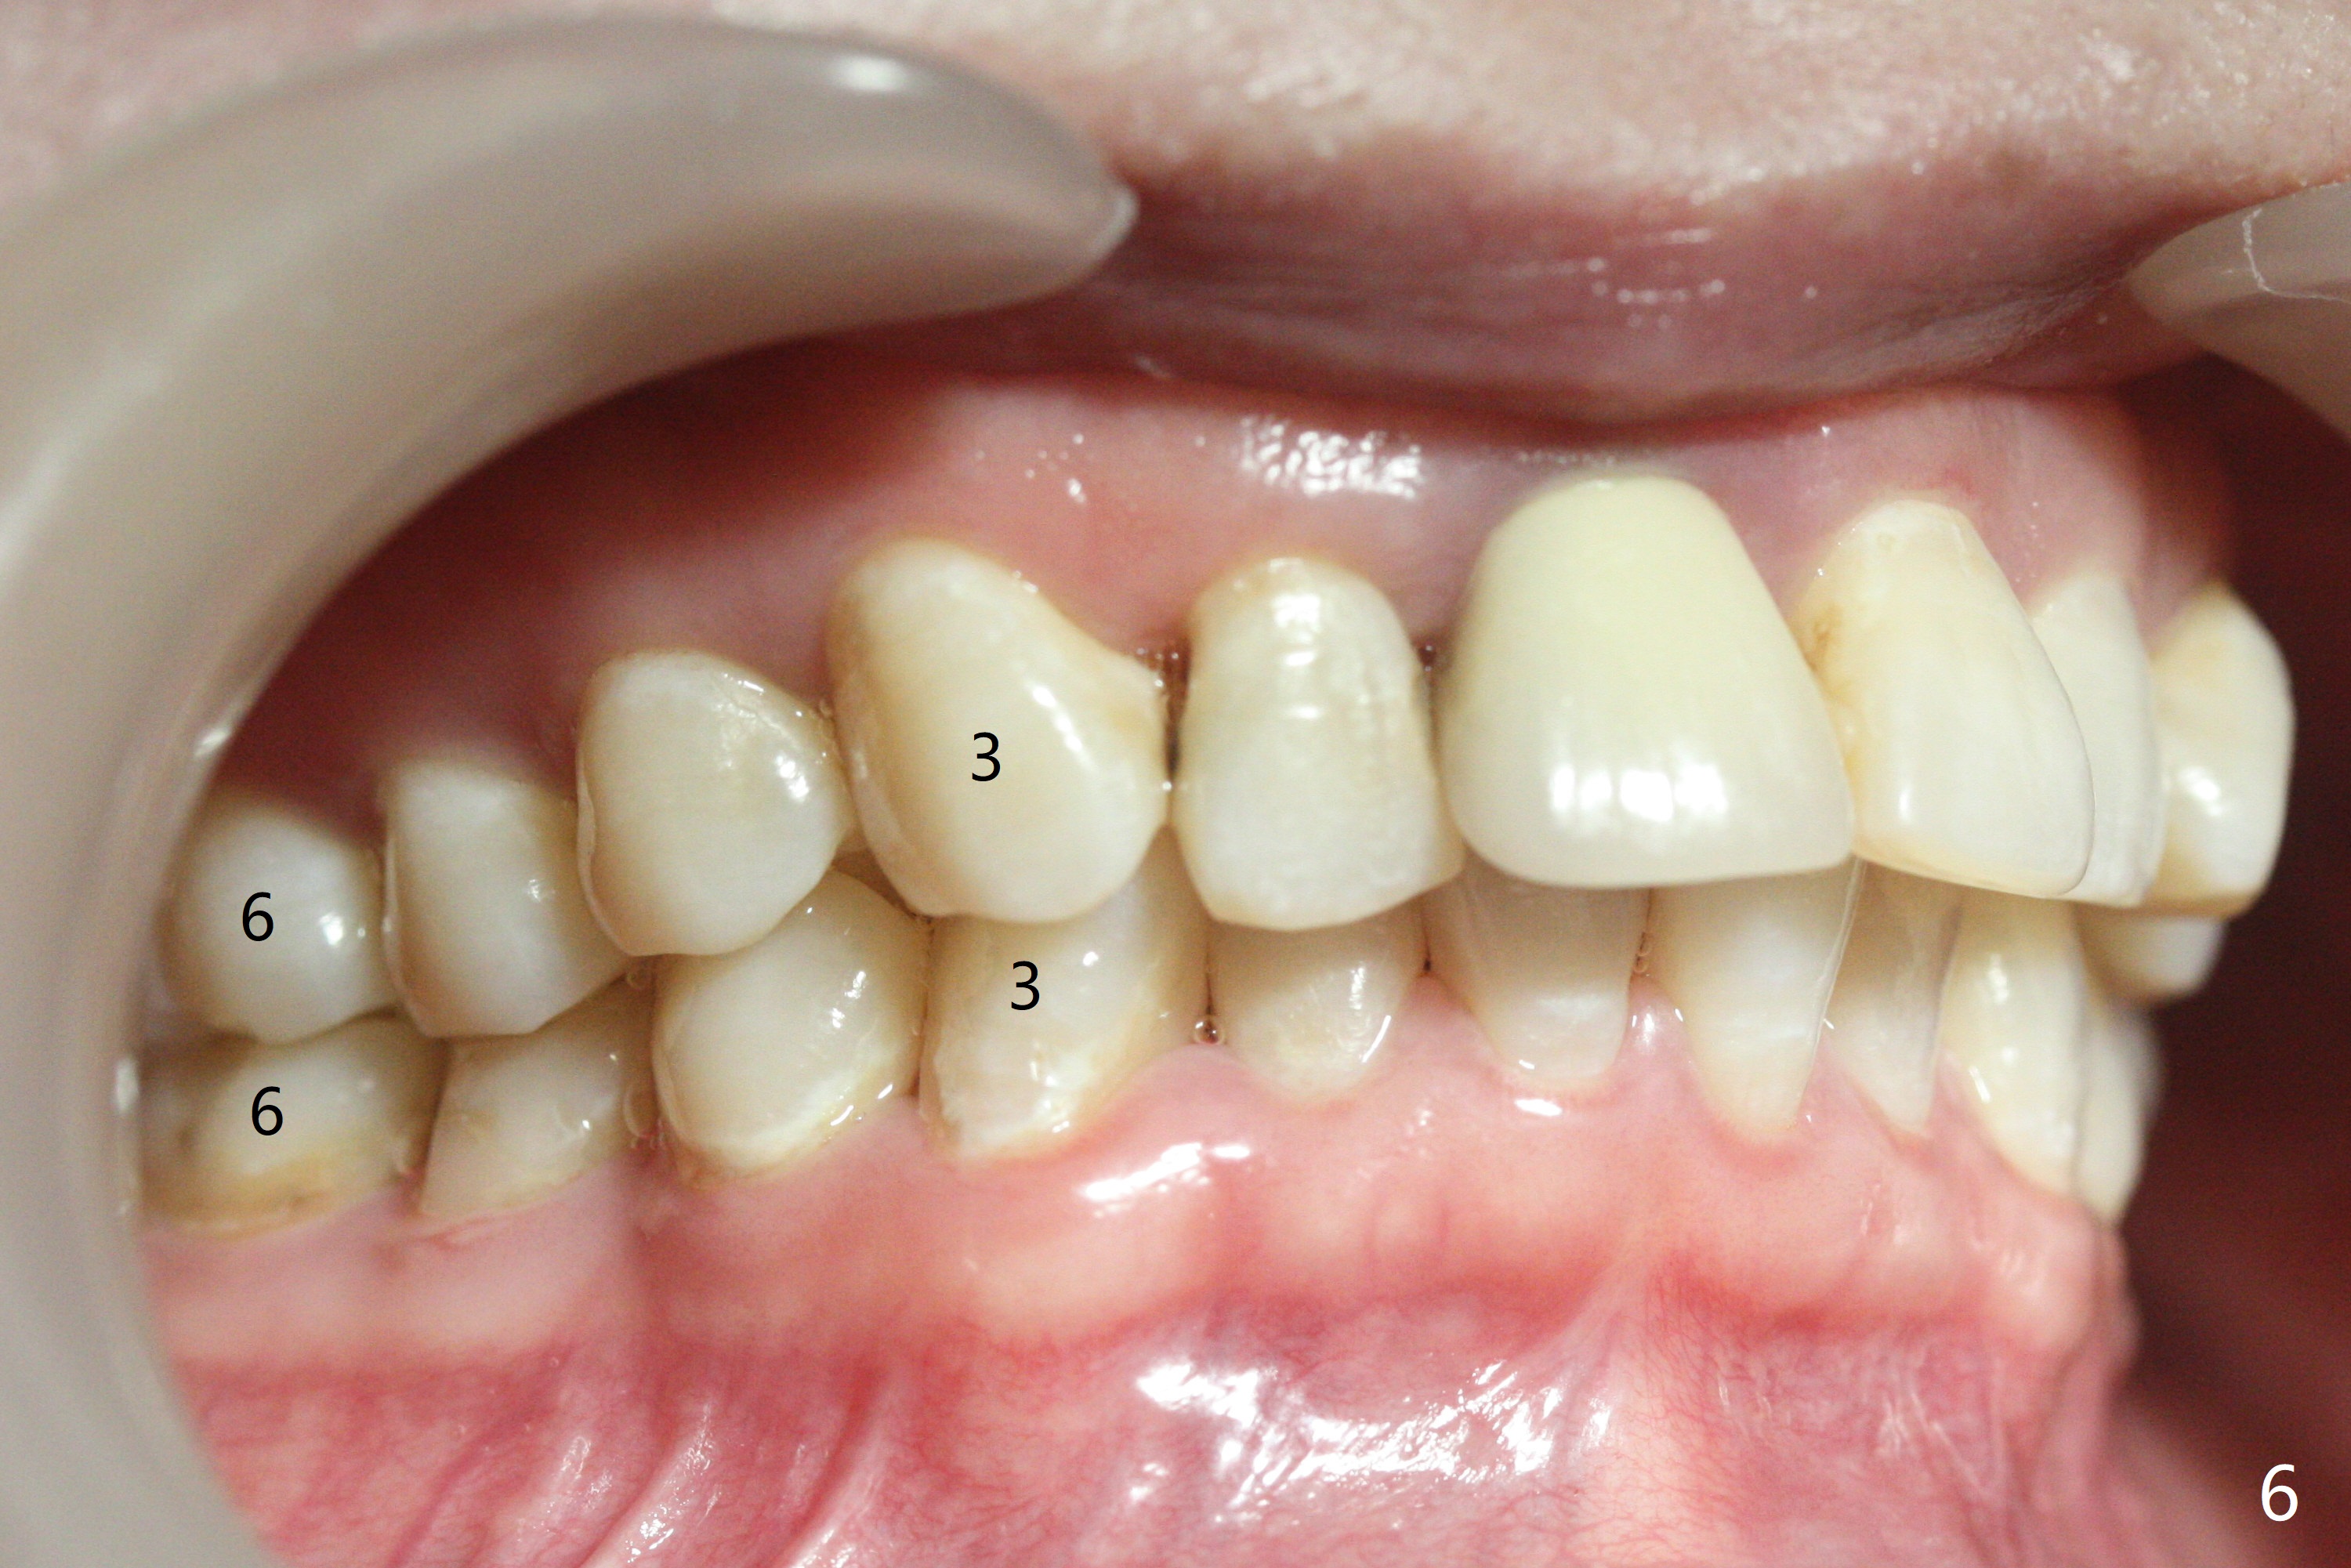

31岁女面部还匀称(图一,二,四,五),但是二类错𬌗严重(图三,六至十),应尽早做二类牵引。压低左上6是 头等大事。磨牙间隙不容易产生,为了避免矫正后磨牙间隙问题,不放置磨牙bands,在右上,右下6,左上6,7放置矫正器,再次使用12niti弓丝。